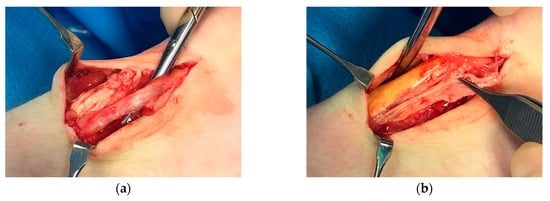

Therefore, the exact prevalence is unknown and might differ between several cohorts. Furthermore, the discrepancy between the studies might be due to different definitions of a partial rupture and the method of detection. In surgical studies, the partial rupture is often diagnosed by the surgeon based on how the tissue looks macroscopically (Figure 1). Some studies use ultrasound or MRI for diagnosis.

Figure 1. (a) Surgical observations in patients with partial Achilles tendon ruptures; (b) higher magnification of longitudinal partial Achilles tendon rupture.